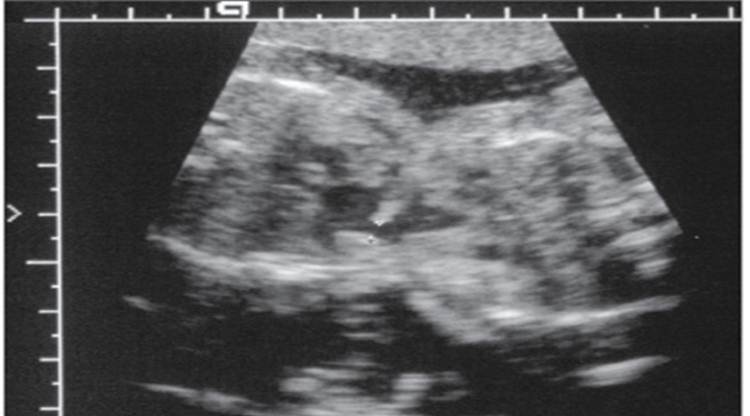

Choroid plexus cysts